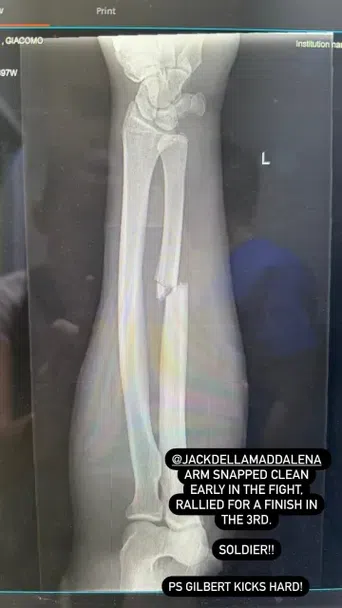

Професионалният ММА боец Джак Дела Мадалена (17-2) записа най-важната победа в кариерата си досега, но с цената на счупена ръка. През изминалия уикенд австралиецът участва в основен двубой от събитието UFC 299, което се проведе в Маями. Той нокаутира бившия претендент за титла в полусредна категория на организацията Джилбърт Бърнс в третия рунд. Мениджърът на боеца, Тим Симпсън, споделя, че Мадалена е изиграл втория и третия рунд със счупена кост на лявата предмишница.

“Ръката на Джак се счупи рано в двубоя. Истински боец! Дуриньо рита здраво!”, написа Симпсън в социалната мрежа Х.